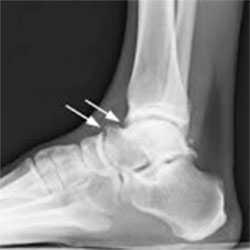

- На рентгенограммах с нагрузкой в боковой проекции могут быть видны остеофиты большеберцовой и таранной костей. В переднем завороте могут быть свободные суставные тела, могут быть признаки перелома остеофитов (рис. 1, А):

Пациенту обязательно назначают рентгенограмму. На рентгенологическом снимке доктор легко увидит остеофиты – костные разрастания, появившиеся из-за воспалительного процесса. Дополнительно выполняется снимок в стрессовом положении. На нем доктор определит, есть ли соударение костей.